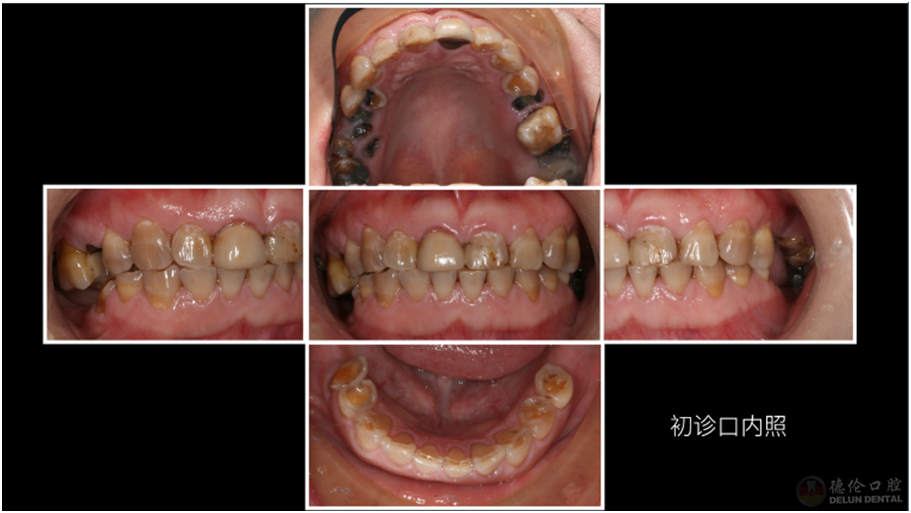

李佳欣医生案例展示

患者症状:牙齿龋坏、四环素牙、牙齿缺失。

治疗方法:治疗牙髓炎和根尖周炎的患牙、拔除残根残冠、升高咬合,种植修复及全冠修复。

术前: